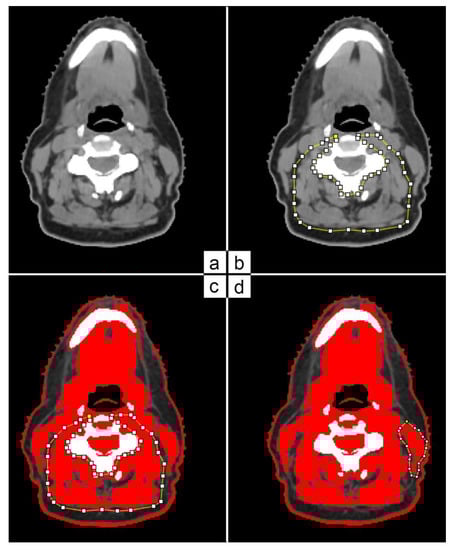

- Gomez-Perez, S.; McKeever, L.; Sheean, P. Tutorial: A Step-by-Step Guide (Version 2.0) for Measuring Abdominal Circumference and Skeletal Muscle From a Single Cross-Sectional Computed-Tomography Image Using the National Institutes of Health ImageJ. J. Parenter. Enter. Nutr. 2020, 44, 419–424. [Google Scholar] [CrossRef]